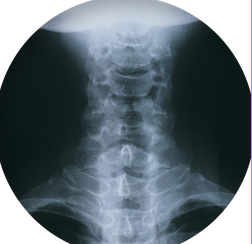

목 디스크 원인

목 디스크의 주요 원인은 디스크의 손상이나 변형으로 인한 것입니다. 목 디스크는 경추나 흉추 디스크에 문제가 생길 때 발생할 수 있으며, 다음과 같은 원인으로 인해 디스크에 손상이 생길 수 있습니다: